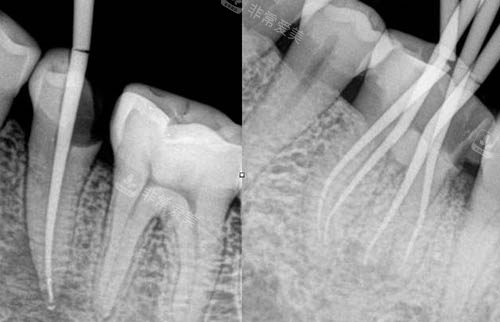

根管治疗ct照片